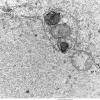

Focal Cortical Dysplasia - ILAE IIb (3)